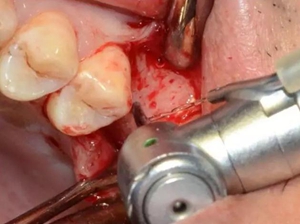

定點定向,初步擴孔

使用止停環(huán)控制深度,逐級預(yù)備打開嵴頂入路。探之竇膜力反饋正常,呈持續(xù)張力。手動探查分離通路周圍竇粘膜并略提升。